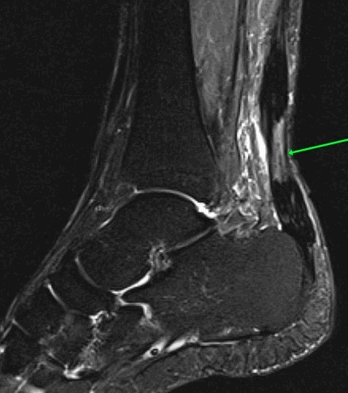

На Т2-fs-ВИ в сагиттальной плоскости определяется разрыва пяточного сухожилия.